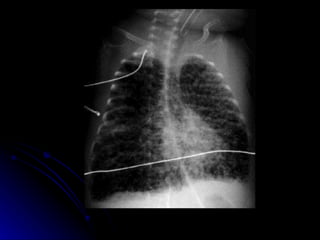

Chronic lung disease Clinical Protracted respiratory insufficiency and oxygen requirement beyond 28th day or 36th week post conceptional age Very preterm with early ventilation for HMD

CLD - Aetiology Ventilation Oxygen toxicity PROM Chorioamnionitis Inflammation Proteolytic enzymes

CLD - prevention Minimise ventilation and oxygen exposure HFOV Early surfactant Corticosteroids  Early extubation

CLD treatment Minimise ongoing barotrauma Nutrition Permissive hypercapnia Diuretics Bronchodilators Corticosteroids - controversial Home oxygen therapy

Chronic lung diseaseClinical Protracted respiratory insufficiency and oxygen requirement beyond 28th day or 36th week post conceptional age Very preterm with early ventilation for HMD

CLD - AetiologyVentilation Oxygen toxicity PROM Chorioamnionitis Inflammation Proteolytic enzymes

CLD - preventionMinimise ventilation and oxygen exposure HFOV Early surfactant Corticosteroids Early extubation

CLD treatment Minimiseongoing barotrauma Nutrition Permissive hypercapnia Diuretics Bronchodilators Corticosteroids - controversial Home oxygen therapy